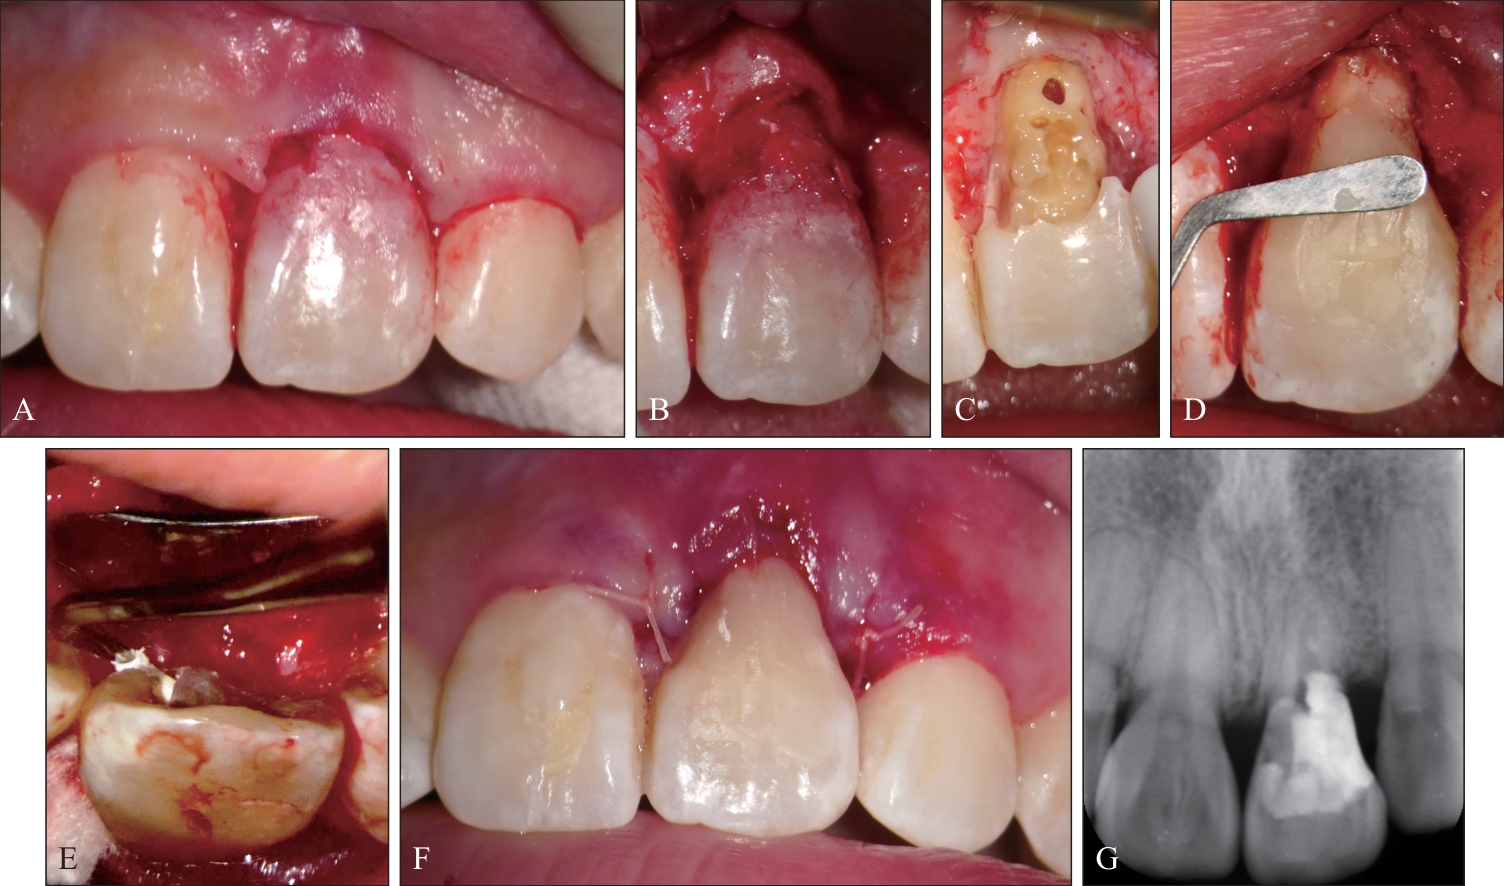

Patel K, Foschi F, Pop I, et al. The use of intentional replantation to repair an external cervical resorptive lesion not amenable to conventional surgical repair[J]. Prim Dent J, 2016, 5(2): 78-83.

Patel S, Foschi F, Condon R, et al. External cervical resorption: part 2—management[J]. Int Endod J, 2018, 51(11): 1224-1238.

Garrido I, Abella F, Ordinola-Zapata R, et al. Combined endodontic therapy and intentional replantation for the treatment of palatogingival groove[J]. J Endod, 2016, 42(2): 324-328.

Yan H, Xu N, Wang HG, et al. Intentional replantation with a 2-segment restoration method to treat severe palatogingival grooves in the maxillary lateral incisor: a report of 3 cases[J]. J Endod, 2019, 45(12): 1543-1549.